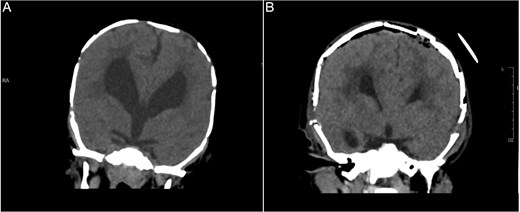

An 11-month-old female infant, born to unrelated Saudi parents, was referred to our facility with unilateral left coronal craniosynostosis, congenital microcephaly, global developmental delay, and a confirmed ZIC1 gene mutation. Comorbidities included a patent foramen ovale, aortopulmonary collateral vessel, G6PD deficiency, and gastroesophageal reflux disease (GERD). At birth head circumference was 29 cm (<first percentile), and progressive skull asymmetry and squinting were noted over time. Developmentally, she exhibited delayed gross and fine motor skills with limited object transfer. On examination, she was alert and visually tracking, with inward ocular deviation (esotropia). Head circumference was 37 cm (<first percentile) with anterior plagiocephaly and towering of the left frontal region (Fig. 1). Pupils were equal and reactive. Fundoscopy and cranial nerve examinations were unremarkable. Gross motor power was within normal limits, except for moderate lower limb spasticity. 3D reconstruction computed tomography (CT) confirmed premature fusion of the left coronal suture with subtle elevation of the superolateral orbital rim, indicating harlequin sign (Fig. 1). Brain CT showed corpus callosum agenesis, colpocephaly, mild ventriculomegaly, right cerebellar and pontine hypoplasia, and a large cisterna magna, consistent with the reported ZIC1-related malformation spectrum (Fig. 2). Given the progressive deformity and concerns of increased intracranial pressure that might be partially contributing to her neurodevelopmental delay, anterior cranial vault expansion with fronto-orbital advancement was performed jointly by the neurosurgery and plastic craniofacial teams (Fig. 3). Intraoperatively, left-sided dural tension was appreciated, indicating localized increased intracranial pressure. The orbital bandeau was reshaped and advanced, achieving immediate cosmetic improvement (Fig. 4). The patient tolerated the surgery well and recovered uneventfully. At her 4-month follow-up, she showed developmental progress including standing without support, purposeful hand use, and verbalization (“Baba”). At 6-month follow-up, brain CT revealed areas of bone resorption which led to the placement of a ventriculo-peritoneal shunt (Fig. 5). The known association of ZIC1 mutation with tethering of the cord prompted spinal magnetic resonance imaging (MRI) screening. Positive findings indicated an untethering procedure, which was successfully done (Fig. 6).

Brain CT showing: A-corpus callosum agenesis, B-colpocephaly, C-mild ventriculomegaly, D-right cerebellar and E-pontine hypoplasia, F-large cisterna magna.